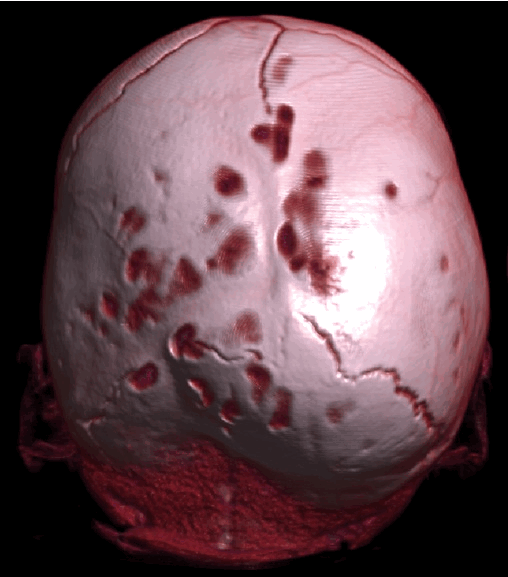

д) Диагностика. Рентгенологические признаки краниосиностозов (Avivet al., 2004) включают заметное усиление пальцевых вдавлений, особенно выраженных при сращении нескольких швов (рис. 5.5). При сагиттальном краниосиностозе обычно отмечается двустороннее преобладание пальцевых вдавлений в области лба. Бороздки от венозных синусов глубокие и хорошо видны. Возможное выраженное увеличение и эрозии спинки турецкого седла. Описанные признаки, которые в некоторых случаях могут выявляться при бессимптомном течении заболевания, свидетельствуют о длительном повышении ВЧД, подтверждаемым непосредственным измерением. Швы не видны, а в области их нормального расположения отмечается гиперостоз.

Тем не менее, на ранней стадии линия шва может быть видна частично или полностью. В таких случаях диагноз устанавливается на основании узкой и прямой линии шва и уплотнения краев шва.

Микроцефалический синостоз (рентгенограмма). Все швы сращены.

Кости свода черепа тонкие с заметными пальцевыми вдавлениями. Венозные синусы глубоко проникают в кость (7-летний мальчик с внутричерепной гипертензией и отеком диска зрительного нерва.

Заболевание одновременно отмечалось у двух сибсов. В обоих случаях умственное развитие не отличалось от нормы).

Рис. №2 а) – вариант нормы

б) – деформация черепа вызванная синостозом (слиянием) лямбдовидного шва слева, указателем показаны множественные пальцевые вдавления (истончение костной ткани, вплоть до появление «дыр»).